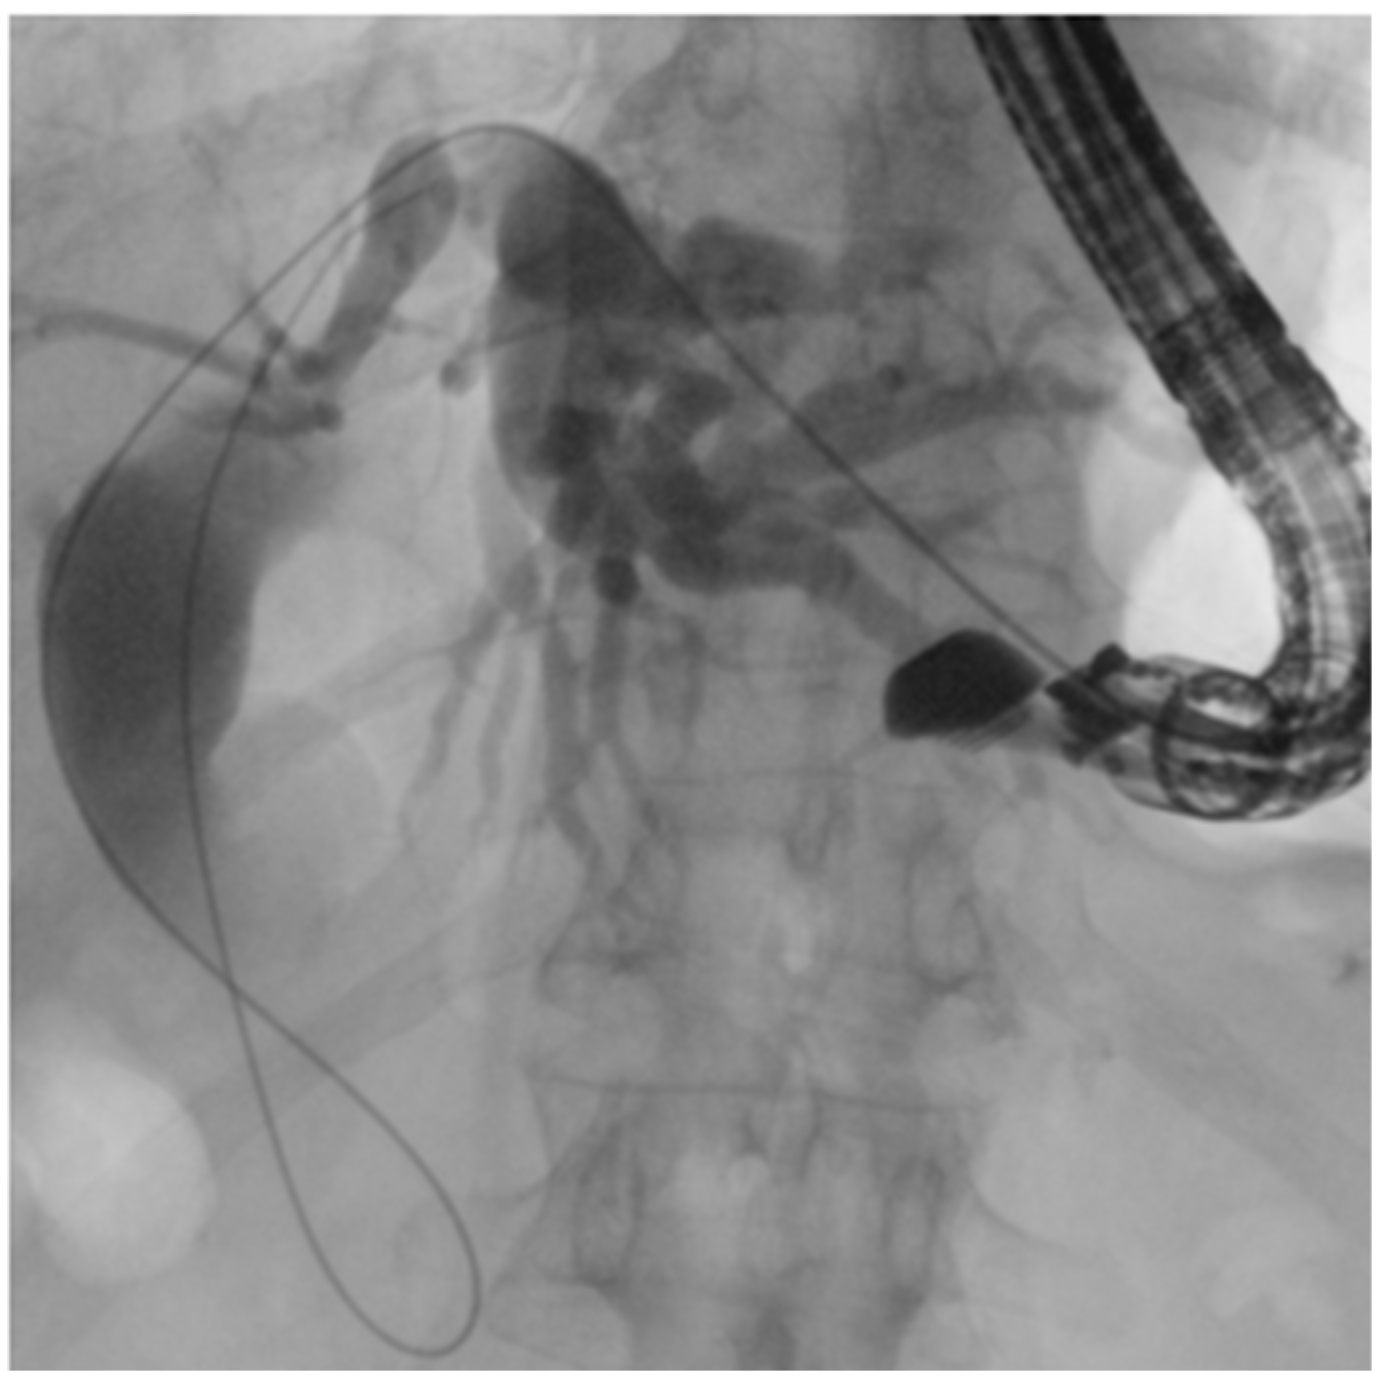

Figure 9. EUS-guided duodenojejunal anastomosis (EDEE): (A) EUS-guided deployment of a LAMS into the jejunal lumen; (B) use of a pediatric colonoscope to reach the biliojejunal anastomosis through the LAMS (indicated by the green arrow); (C) fcSEMS protruding from the anastomosis.

In this technique, a LAMS is used to create an anastomosis between the stomach or duodenum and the afferent biliary limb, thus restoring endoscopic access to the biliary anastomosis with a standard duodenoscope.

By providing a permanent and reusable access route, the entero-enteric bypass enables repeated interventions over time with standard devices. Moreover, the possibility to reach directly the anastomotic area with large-caliber scopes (e.g., pediatric colonoscope with 3.8 mm operative channel) also permits treatment of the most challenging cases with the full standard equipment (Figure 9).